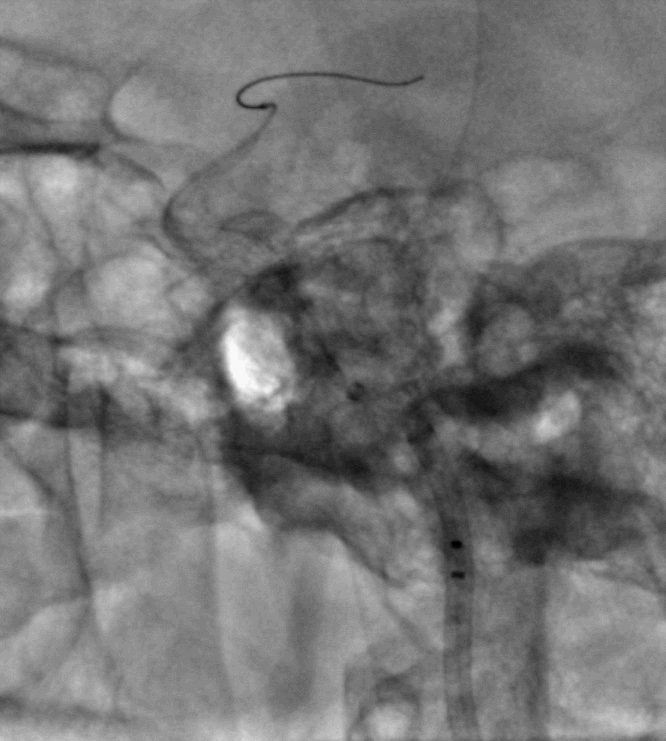

手术过程

Cat5完全释放支架后,拉推送杆后支架近端打开,后将Cat5跟进血流导向装置内尝试“按摩”,支架整体贴壁不够理想。

Cat5通过后海绵窦段狭窄即较前改善

Cat5提供稳定通路,引入3.5mm×10mmHiryu球囊扩张由远端及近端扩张狭窄段及支架贴壁欠佳处

造影示狭窄及贴壁较前进一步改善

导丝成袢,继续“按摩”改善贴壁

“按摩”后再次造影,C2段狭窄仍较明显且贴壁欠佳

再次引入球囊扩张近端

扩张后再次复查造影示支架打开及贴壁较前明显改善

标准正侧位造影未见远端血管栓塞

稀释造影提示支架贴壁可,狭窄改善